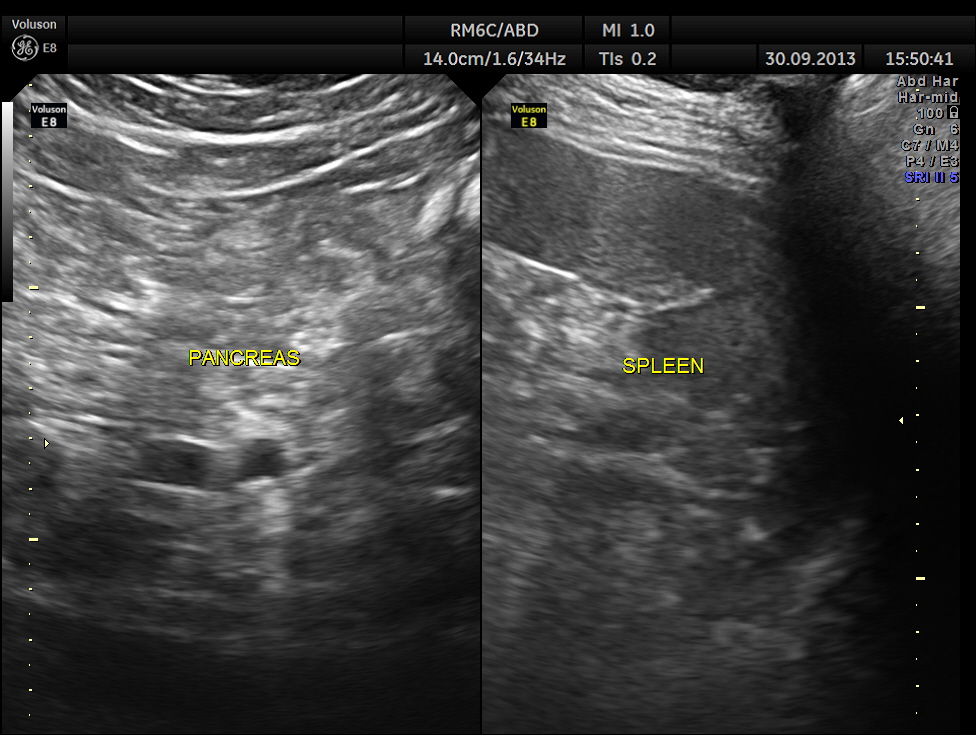

This was a 57 year old gentleman , with complaints of difficulty in passing urine and dysuria of 1 month duration.

His upper abdominal scan was normal . His left kidney was normal.